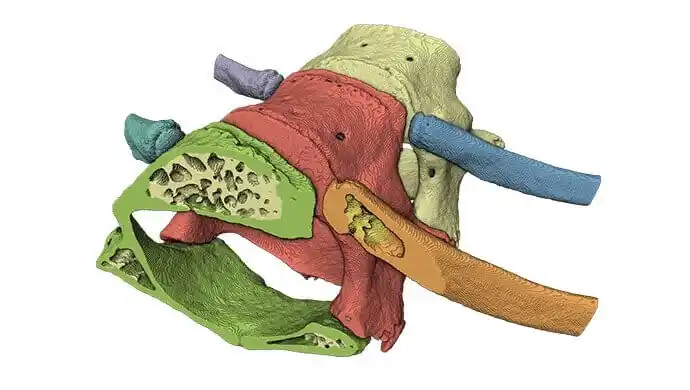

XImagePAQ – Advanced Image processing and quantification

This extension provides advanced tools for image enhancement, simplified and automated segmentation, extensive measurement and quantification of objects, cells, and tissue features. Learn more